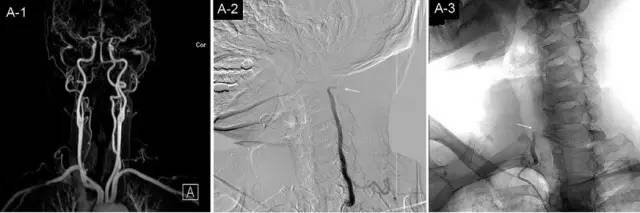

从影像学来看颈椎病为何会引起眩晕